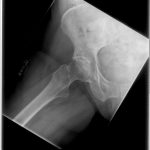

Pre-Op AP Pelvis

Harris Hip Score 37 (max=100) | Oxford Hip Score 19 (max=48)